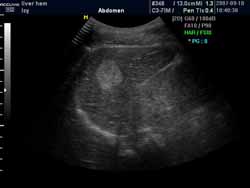

(血管瘤超聲表現(xiàn)可見高回聲血管團(tuán)影)

(超聲穿刺針直接對瘤體進(jìn)行注射治療)